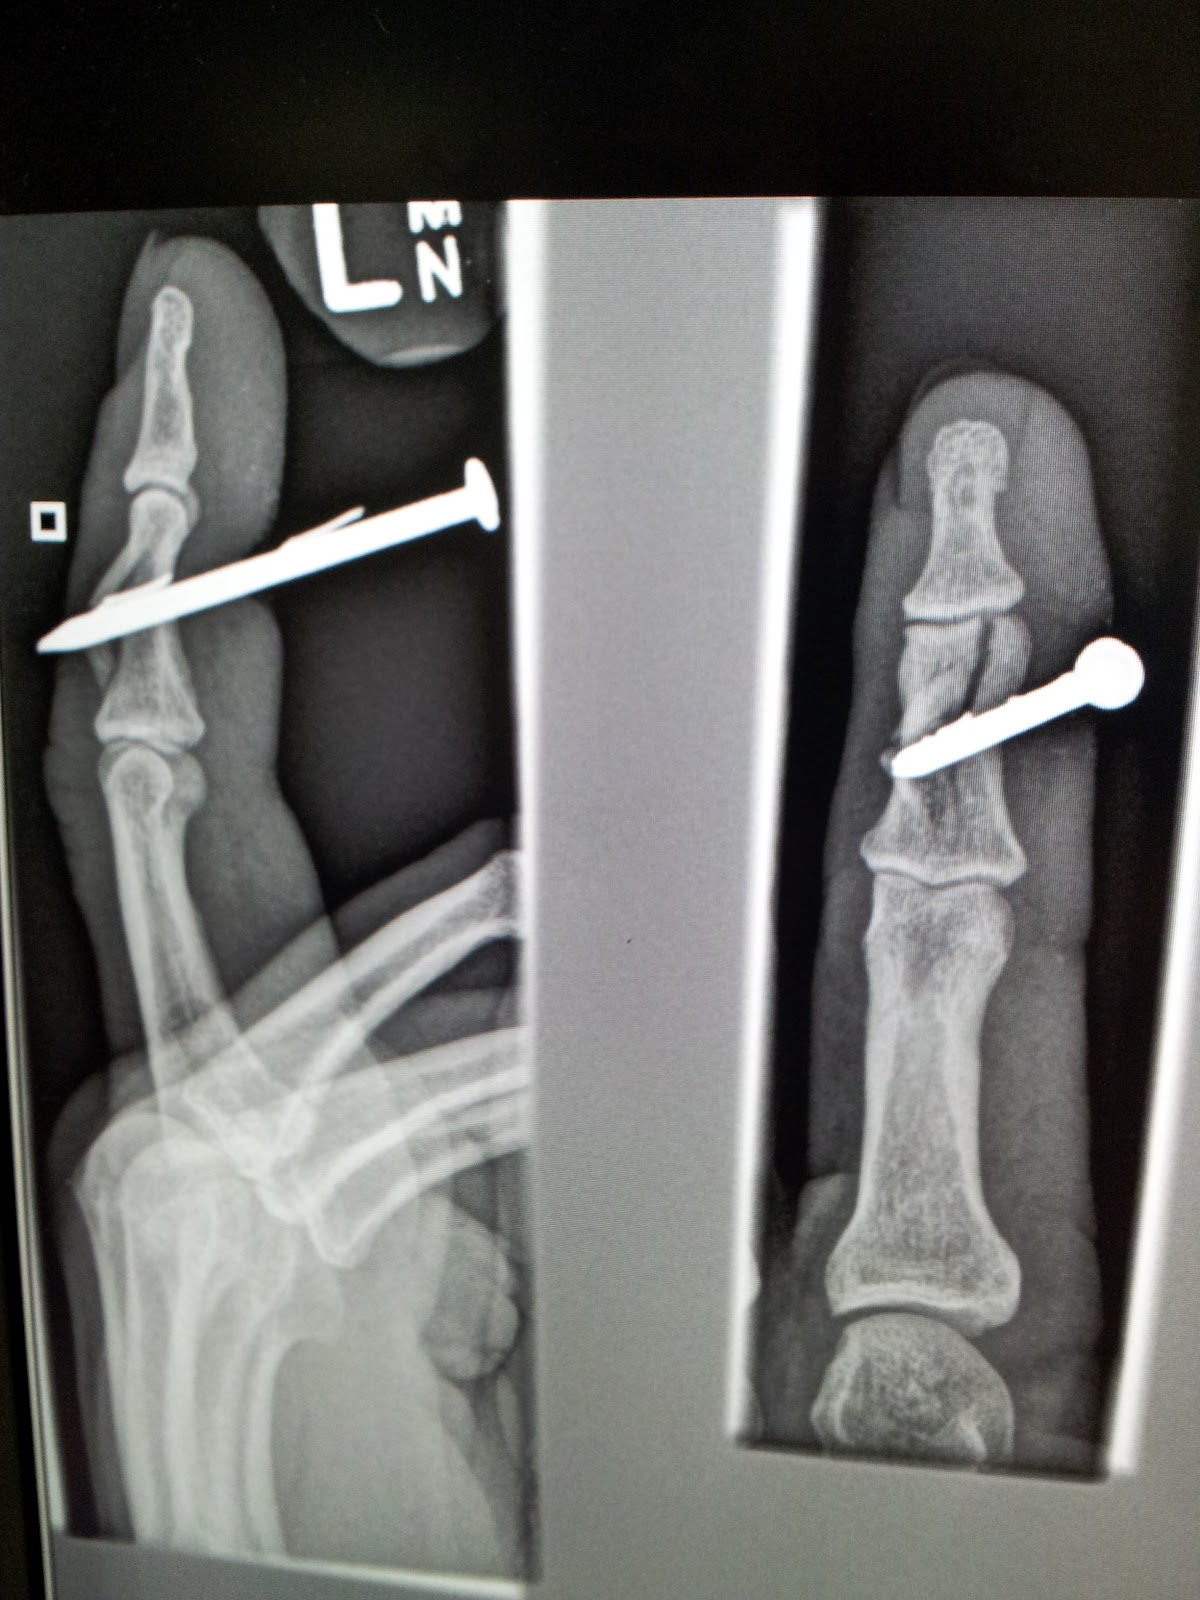

| Finger nail…haha..get it?? |

| Finger nail #2, with open fracture |